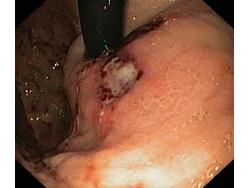

Krwawienie